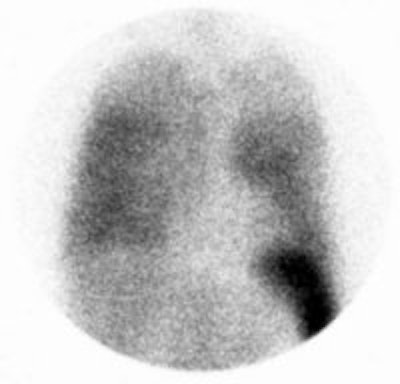

Crohns disease with abscess: The patient below had Crohns disease and was being evaluated for persistent fevers and elevated white blood cell count. The In111-WBC exam demonstrated a very intense focal accumulation of labeled WBC's in the mid pelvis (black arrow). Large bowel activity can also be seen, however, these images were performed at 24 hours following injection and cells sloughed from sites of active inflammation can be carried distally causing the appearance of colitis. The CT scan (right) had actually been performed prior to the white blood cell study and had been interpreted as negative for abscess. In retrospect, the abscess can be seen on the CT scan (white arrow), but was missed because of poor bowel opacification. Click CT to view more images. |

|